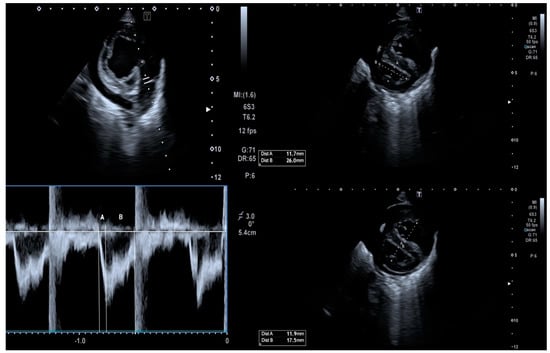

2.2.2. Cardiac Status Assessment

4.2. Cardiac Status in Acute Bronchiolitis